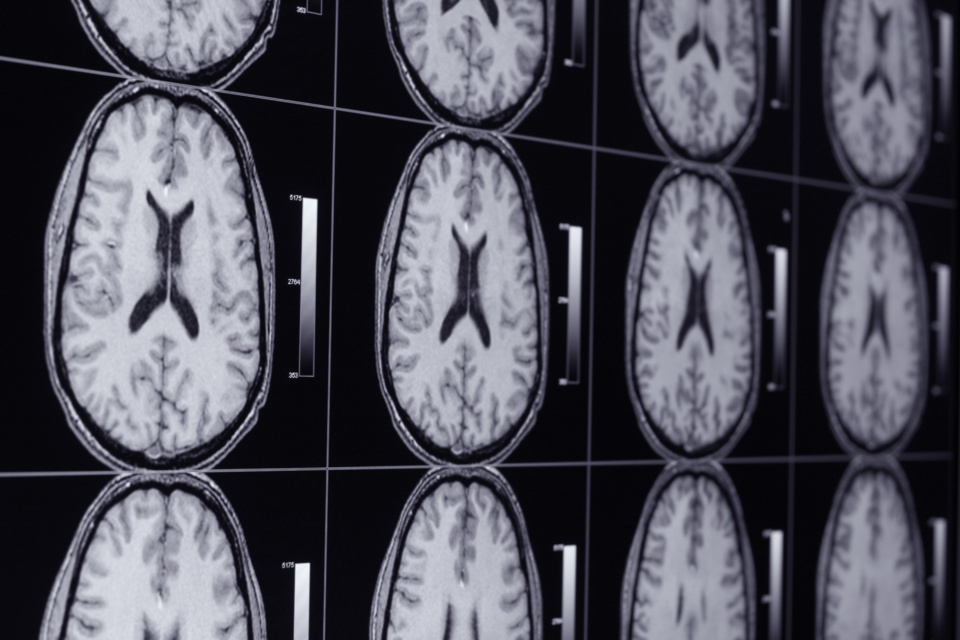

El estudio fue realizado a un grupo de 36 voluntarios. En primer lugar se sometieron a una serie de ejercicios de memorización a partir de la asociación de pares de palabras, como por ejemplo “montaña-América”. A continuación debían intentar olvidar la segunda palabra a partir de uno de los dos procesos –supresión y sustitución. A lo largo del experimento se utilizaron técnicas de imagen por resonancia magnética funcional (fMRI) para analizar las dos formas en que olvidaban.

Los resultados demostraron que al suprimir un recuerdo, el hipocampo -región para el recuerdo de eventos pasados- quedaba inactivo. Sin embargo, al sustituir unos recuerdos por otros se ponen en marcha dos regiones del cerebro distintas que actúan para borrar recuerdos indeseados y traer otros a la memoria.